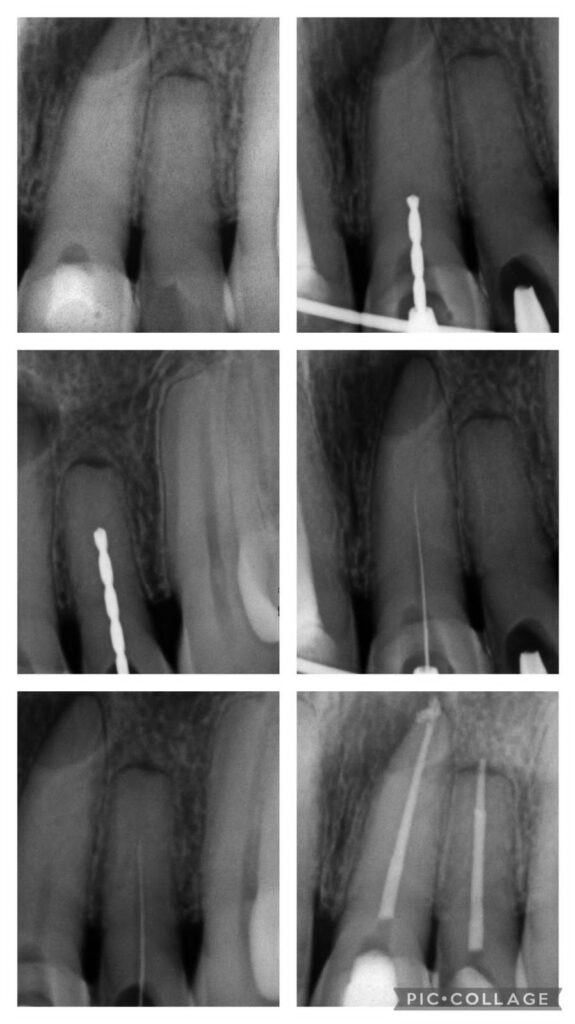

Faça parte do seleto grupo de planejadores que utilizam a revolucionária metodologia para gerar guias de acesso aos casos mais complexos de canais calcificados como quarto canal e incisivos inferiores

Sistema que alia ferramentais específicos e metodologia de planejamento que evita fratura de brocas e preserva até 50% a mais de estrutura dentinaria em relação a broca de 1.3mm

– Planejamento de casos com brocas 0.6, 0,8 e 1.0mm

– Apresentação de casos clínicos realizados com brocas 0.6 e 0.8 (exames iniciais, planejamento e exames finais)

Mentoria de 9 horas em três módulos de 3 horas para serem planejados e impressas as guias de três casos; sendo 2 dois de casos complexos (4º canal e incisivo inf.).